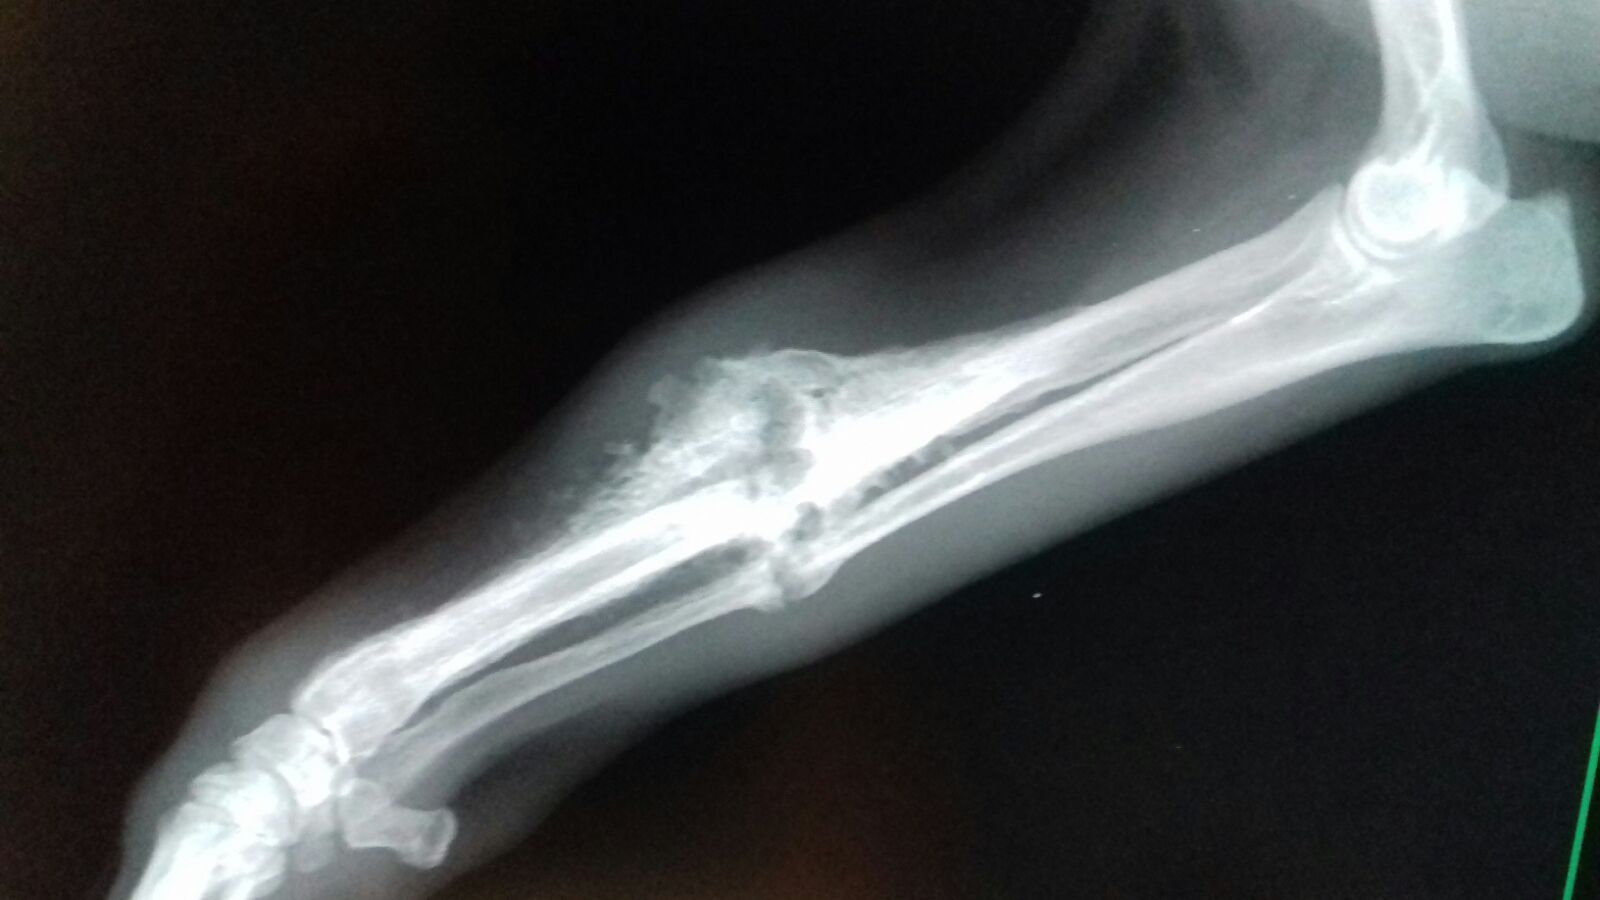

Im Rahmen der Kastration wurde auch Ricardas rechtes Vorderbein geröntgt. Die italienischen Tierärzte möchten nicht mehr daran rühren, aber wir lassen die Röntgenaufnahmen noch in Deutschland von einem Spezialisten für Orthopädie begutachten und hoffen, dass der lieben Hündin doch noch geholfen werden kann!